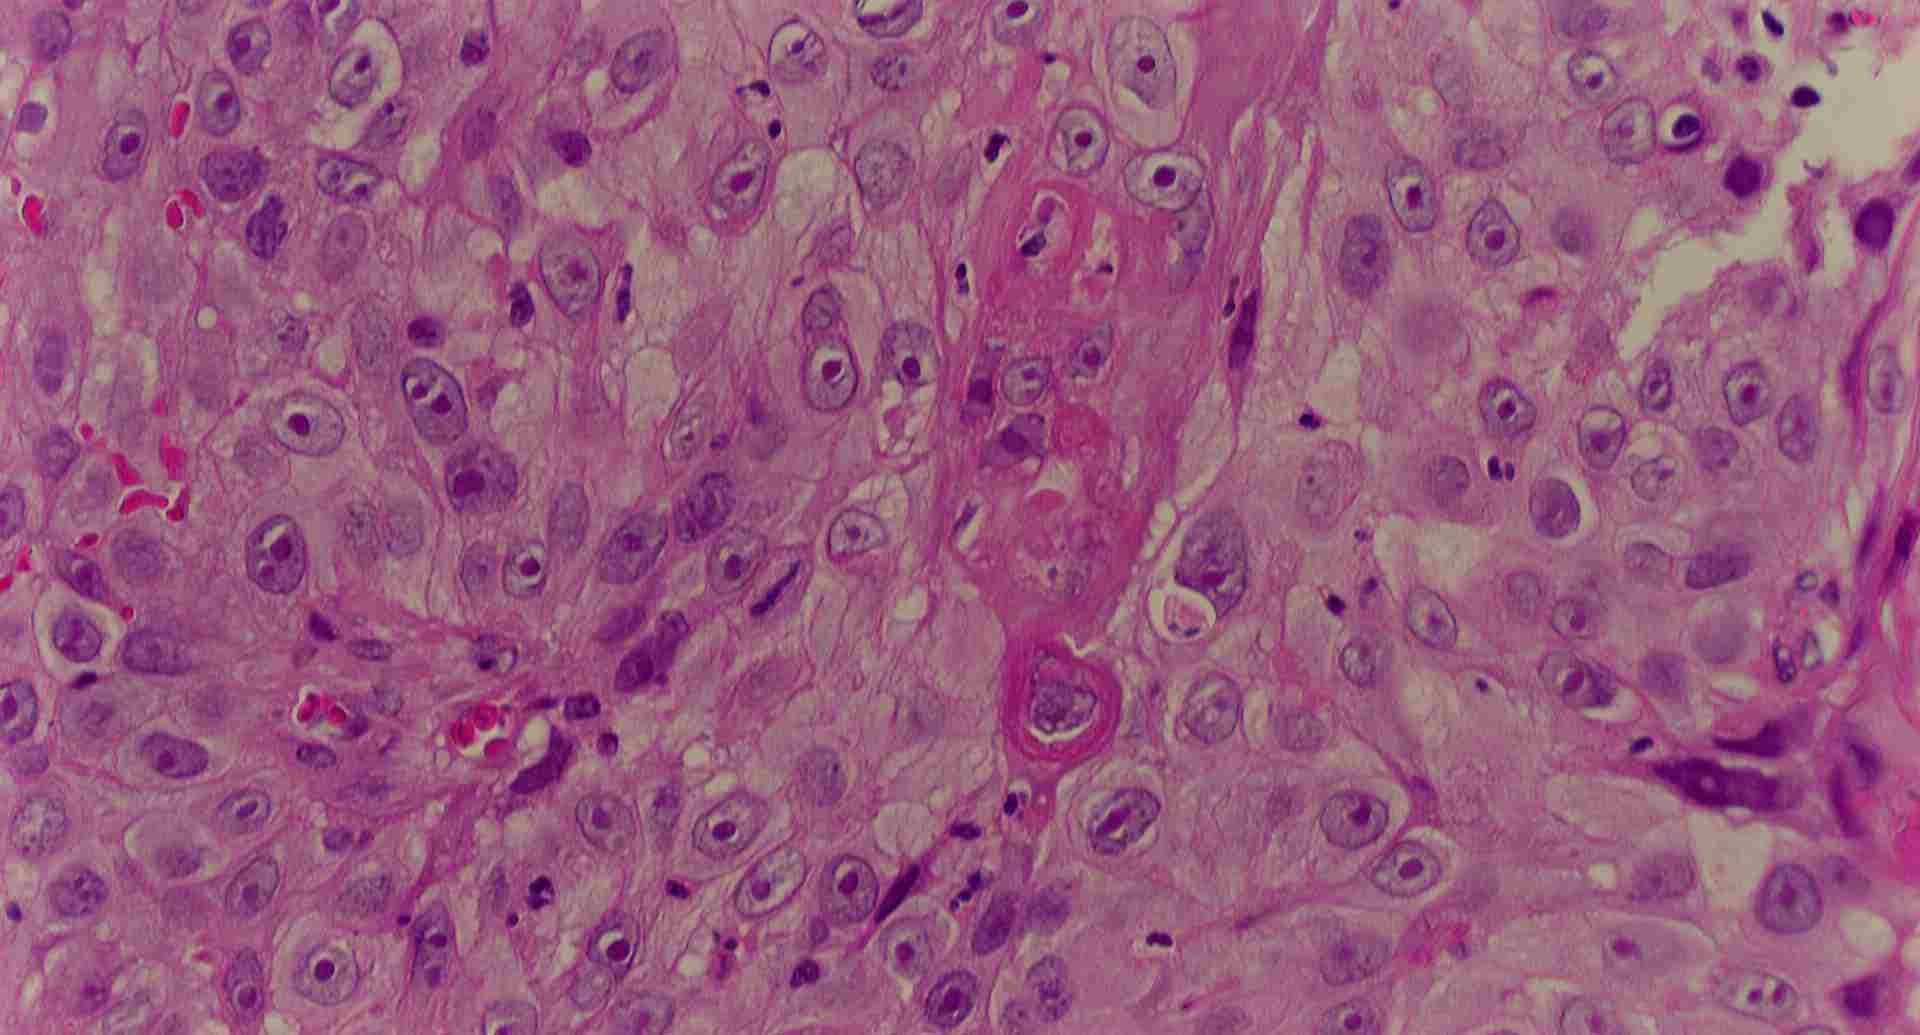

標本の説明

標本10